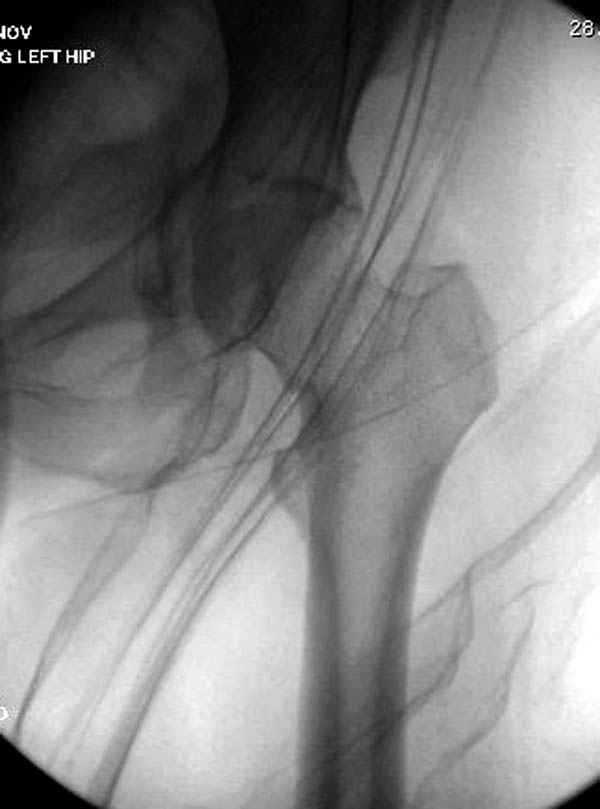

Уважаемые коллеги! С прошедшеми Вас праздниками. Теперь ближе к трудовым будням. Поступила 16 летняя девушка неделю назад. Механизм травмы падение с 5 этажа. Краткий диагноз:закрытый перелом левой ключицы, левого плеча, закрытый вертикально и ротационно нестабильный перелом костей таза:закрытый перелом левой подвздошной кости, переломы лонной кости справа, перелом обоих колонн вертлужной впадины слева;субкапитальный перелом шейки левой бедренной кости со смещением. По тактике лечения таза возникли следующие вопросы: 1. С чего начать - фиксации переломов вертлужной впадины или устранения деформаций таза? 2. Надо ли фиксировать шейку или фиксировать бедро в аппарате вместе с тазом, а после сращения таза планировать ТЭП ТБС? Если имеются еще какие подводные камни, будем рады выслушать.Спасибо.

На снимке ацетабулума редко встречающийся очень низкий перелом, наверное, трудно было репозицию через один доступ? Перелом как бы замкнулся в квадрилатеральной поврехности.

Ничего такого особенного в переломе вертлужной впадины не опознал. Транстектальный перелом хорошо репонируется щипцами, установленными через седалищную вырезку.

В положении на спине подвздошным и надлобковым доступом восстанавливается тазовое кольцо, фиксация пластинами. При хорошей репозиции может улучшиться конгруэнтность в суставе.

Затем, если положение хорошее, закрытый остеосинтез шейки винтами.

Если нет - в положении на боку, синтез задней колонны из наружно-латерального доступа и синтез головки винтами, но уже под визуальным контролем.